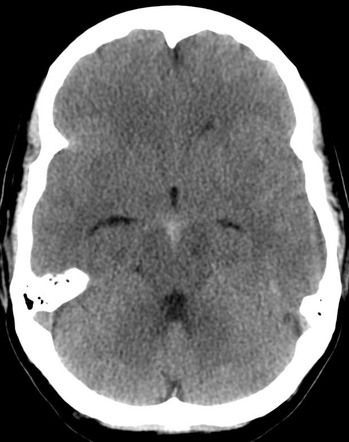

Subarachnoid hemorrhage most commonly occurs secondary to rupture of berry aneurysm. It presents with severe headache. Following are the CT findings of subarachnoid hemorrhage: - hyperdensity in subarachnoid space - blood present in interpeduncular fossa, manifested as triangular area of hyperdensity Reference: https://radiopaedia.org/articles/subarachnoid-haemorrhage Image via: https://radiopaedia.org/articles/subarachnoid-haemorrhage